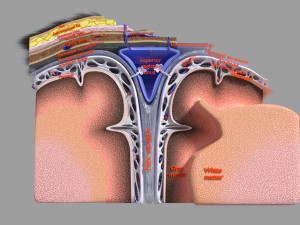

A blend model of brain along with its covering layers (meninges), skull bone and scalp labelled in detail and anatomically precise. The parts depicted are white, gray, pia, arachnoid, dura, bone, skin, fat, aponeurosis, periosteum, falx cerebri and more.

The material is high resolution image textures and normal maps based on non overlapping UVs. The texture and normal maps are packed with the blend file itself.